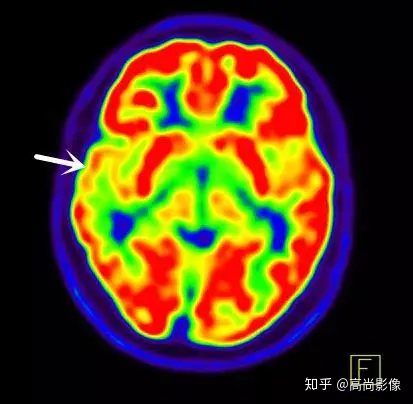

局部18F-FDG代謝顯像主要應(yīng)用于無創(chuàng)定位癲癇病灶。

在國際上,18F-FDG代謝顯像是無創(chuàng)定位癲癇病灶的標(biāo)準(zhǔn)。

發(fā)作間期癲癇灶呈代謝減低

發(fā)作期癲癇灶呈代謝增高